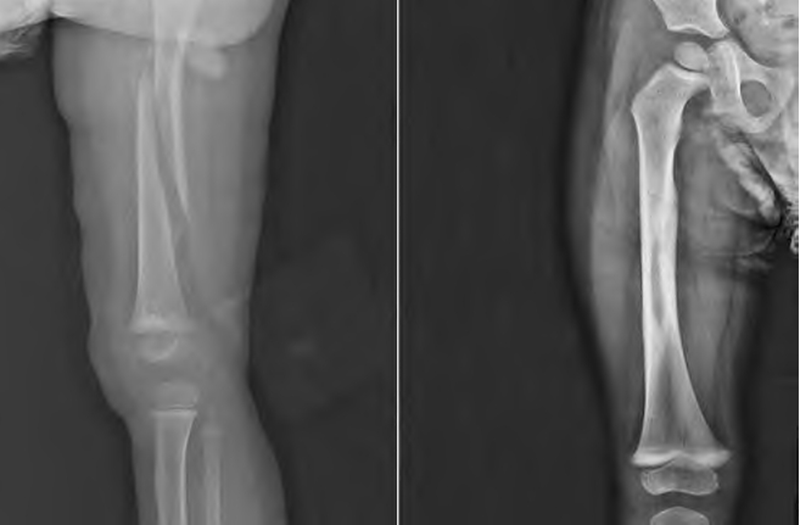

儿童股骨干骨折是儿童骨折中较为常见的一种骨折,指股骨小转子下至股骨髁上之间的骨折,约占儿童全身骨折的1.4%~1.7%,通常以坠落伤、运动意外受伤和交通事故引起为主。儿童股骨干骨折主要发生于2个年龄段,第一个年龄段为1~3岁,主要为低能量损伤;第二个年龄阶段为青春期早期,主要为高能量损伤。

小于3岁的儿童股骨干骨折以保守治疗为主,大于3岁的儿童股骨干骨折随着弹性髓内钉的临床应用,治疗方式也越来越趋向手术治疗。对于儿童股骨干骨折的治疗原则,主要是恢复股骨轴线与旋转畸形,而不是非要强调解剖复位。根据美国骨科医师协会的临床实践指南,最佳治疗方法是要根据患儿年龄和骨折类型来选择。

目前,尚无通用的儿童股骨干骨折分类、分型系统。根据骨折位置分为:近段骨折、中段骨折、远段骨折;按照骨折断端情况分为:横型骨折、螺旋型骨折、斜型骨折、粉碎型骨折;按照软组织损伤后骨折断端是否与外界相通分为:闭合性、开放性骨折。